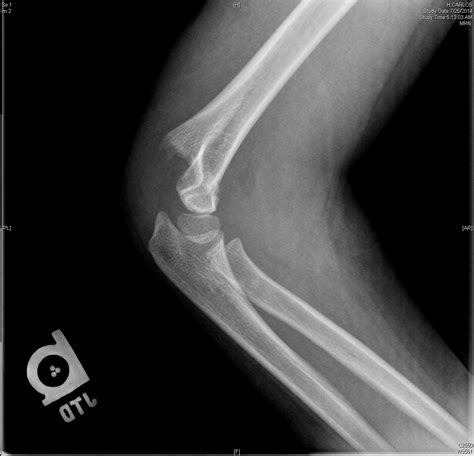

Diagnosing a supracondylar humerus fracture involves a thorough physical examination and imaging studies. The healthcare provider will assess the elbow for signs of injury, such as swelling, deformity, and tenderness. Imaging studies, such as X-rays, are crucial for confirming the diagnosis and determining the type and severity of the fracture.

X-rays are typically taken from multiple angles to provide a comprehensive view of the fracture. In some cases, additional imaging studies, such as a CT scan or MRI, may be necessary to assess the extent of the injury and plan the appropriate treatment.

Supracondylar humerus fractures are classified based on the direction of the fracture line and the displacement of the bone fragments. The most commonly used classification system is the Gartland classification, which includes three types:

Type II Displaced fracture with posterior angulation of the distal fragment

Type III Completely displaced fracture with no cortical contact between the fragments